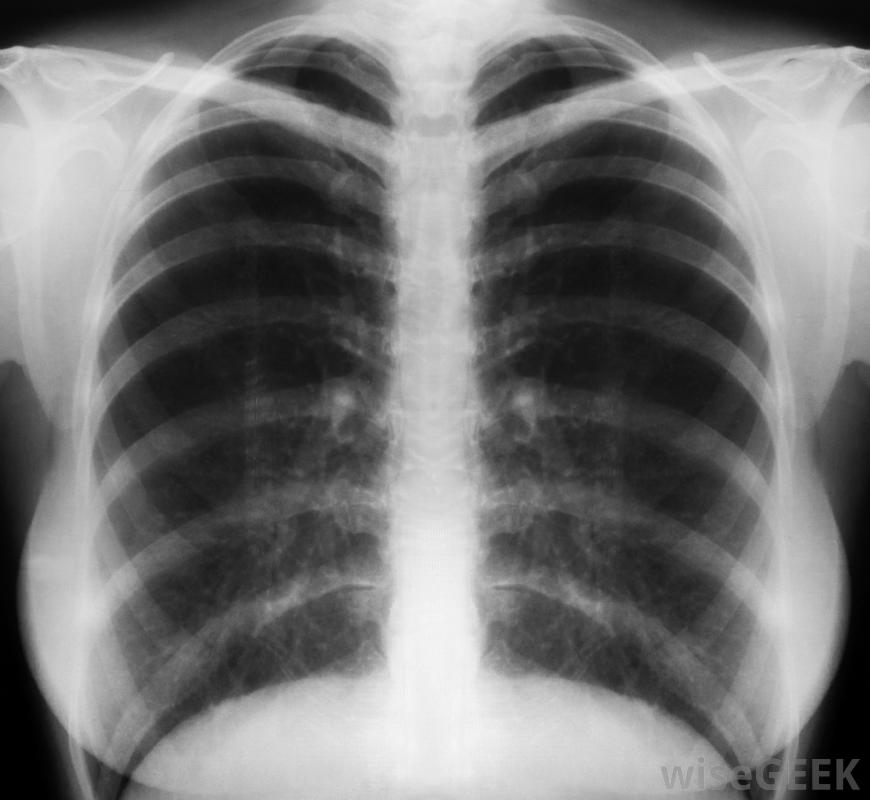

胸部x光片可帮助诊断肺结核了解肺结核(TB)皮肤测试结果呈阳性后会发生什么,了解什么是结核病测试非常重要。在PPD测试中,也称为mantoux测试,在皮肤下注射少量结核病抗原-结核菌素。注射后48到72小时检查注射部位,检查皮肤有无隆起区域,称为硬结。如果结核病皮肤试验呈阳性,这意味着病人对引起肺结核的细菌有反应,但并不一定意味着病人有症状或活动性疾病。

需要进一步的诊断在肺结核皮试呈阳性后。如果肺结核皮试结果呈阳性,则第一次检查通常是胸部X光片。X光片可以确定肺部是否有浸润或病变,这可能指示活动TB通常也会检查症状清单,以确定是否有结核病的症状,如体重减轻、咳血、发烧和盗汗。如果胸部X光检查正常,没有症状,通常不需要进一步检查